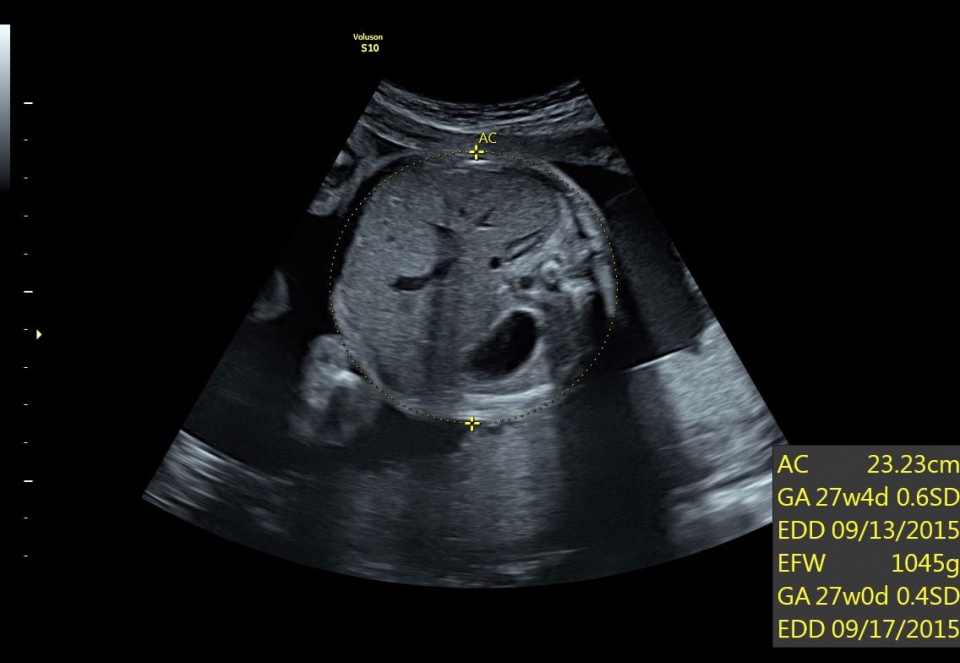

• SonoBiometry (Полуавтоматическая биометрия): Эта технология позволяет проводить измерения биометрических параметров плода, таких как бипариетальный размер, окружность головы, окружность живота, длина бедра и длина плеча. Она упрощает процесс получения точных и надежных измерений.

• SonoBiometry (автоматическое измерение BPD, AC, HC, HL, FL)